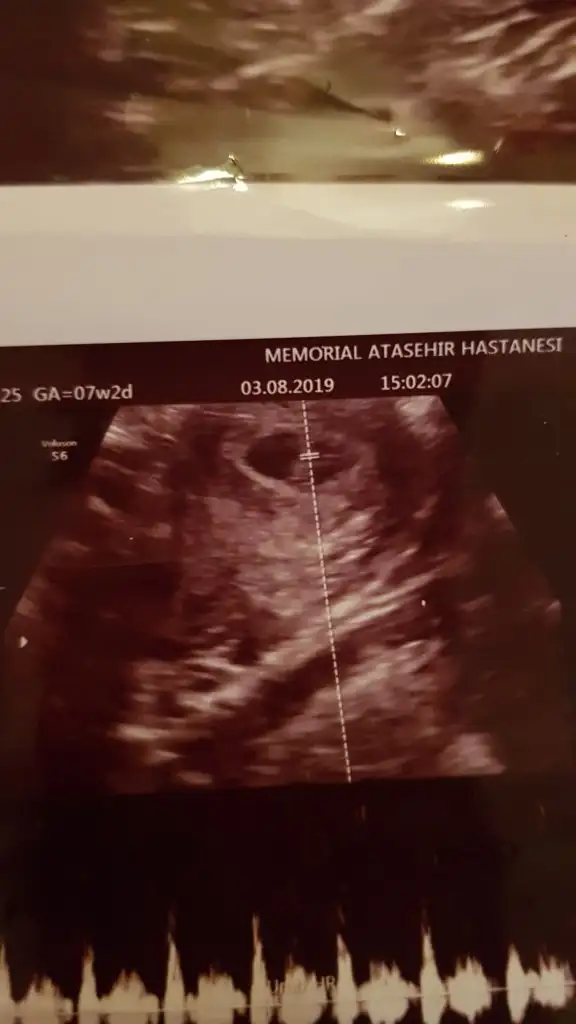

8 buçuk haftalik6 yada 7 haftalık olmalı buna göre erkek ama nub teorisi biraz daha netlik varoda 11 yada 12 hafta usg olmalı

Buna göre kız ama 6 yada 7 hafta usg olmalıBana da bir yorum yapabilir mısınız arkadaşlar ? 8 hafta 1 günlük